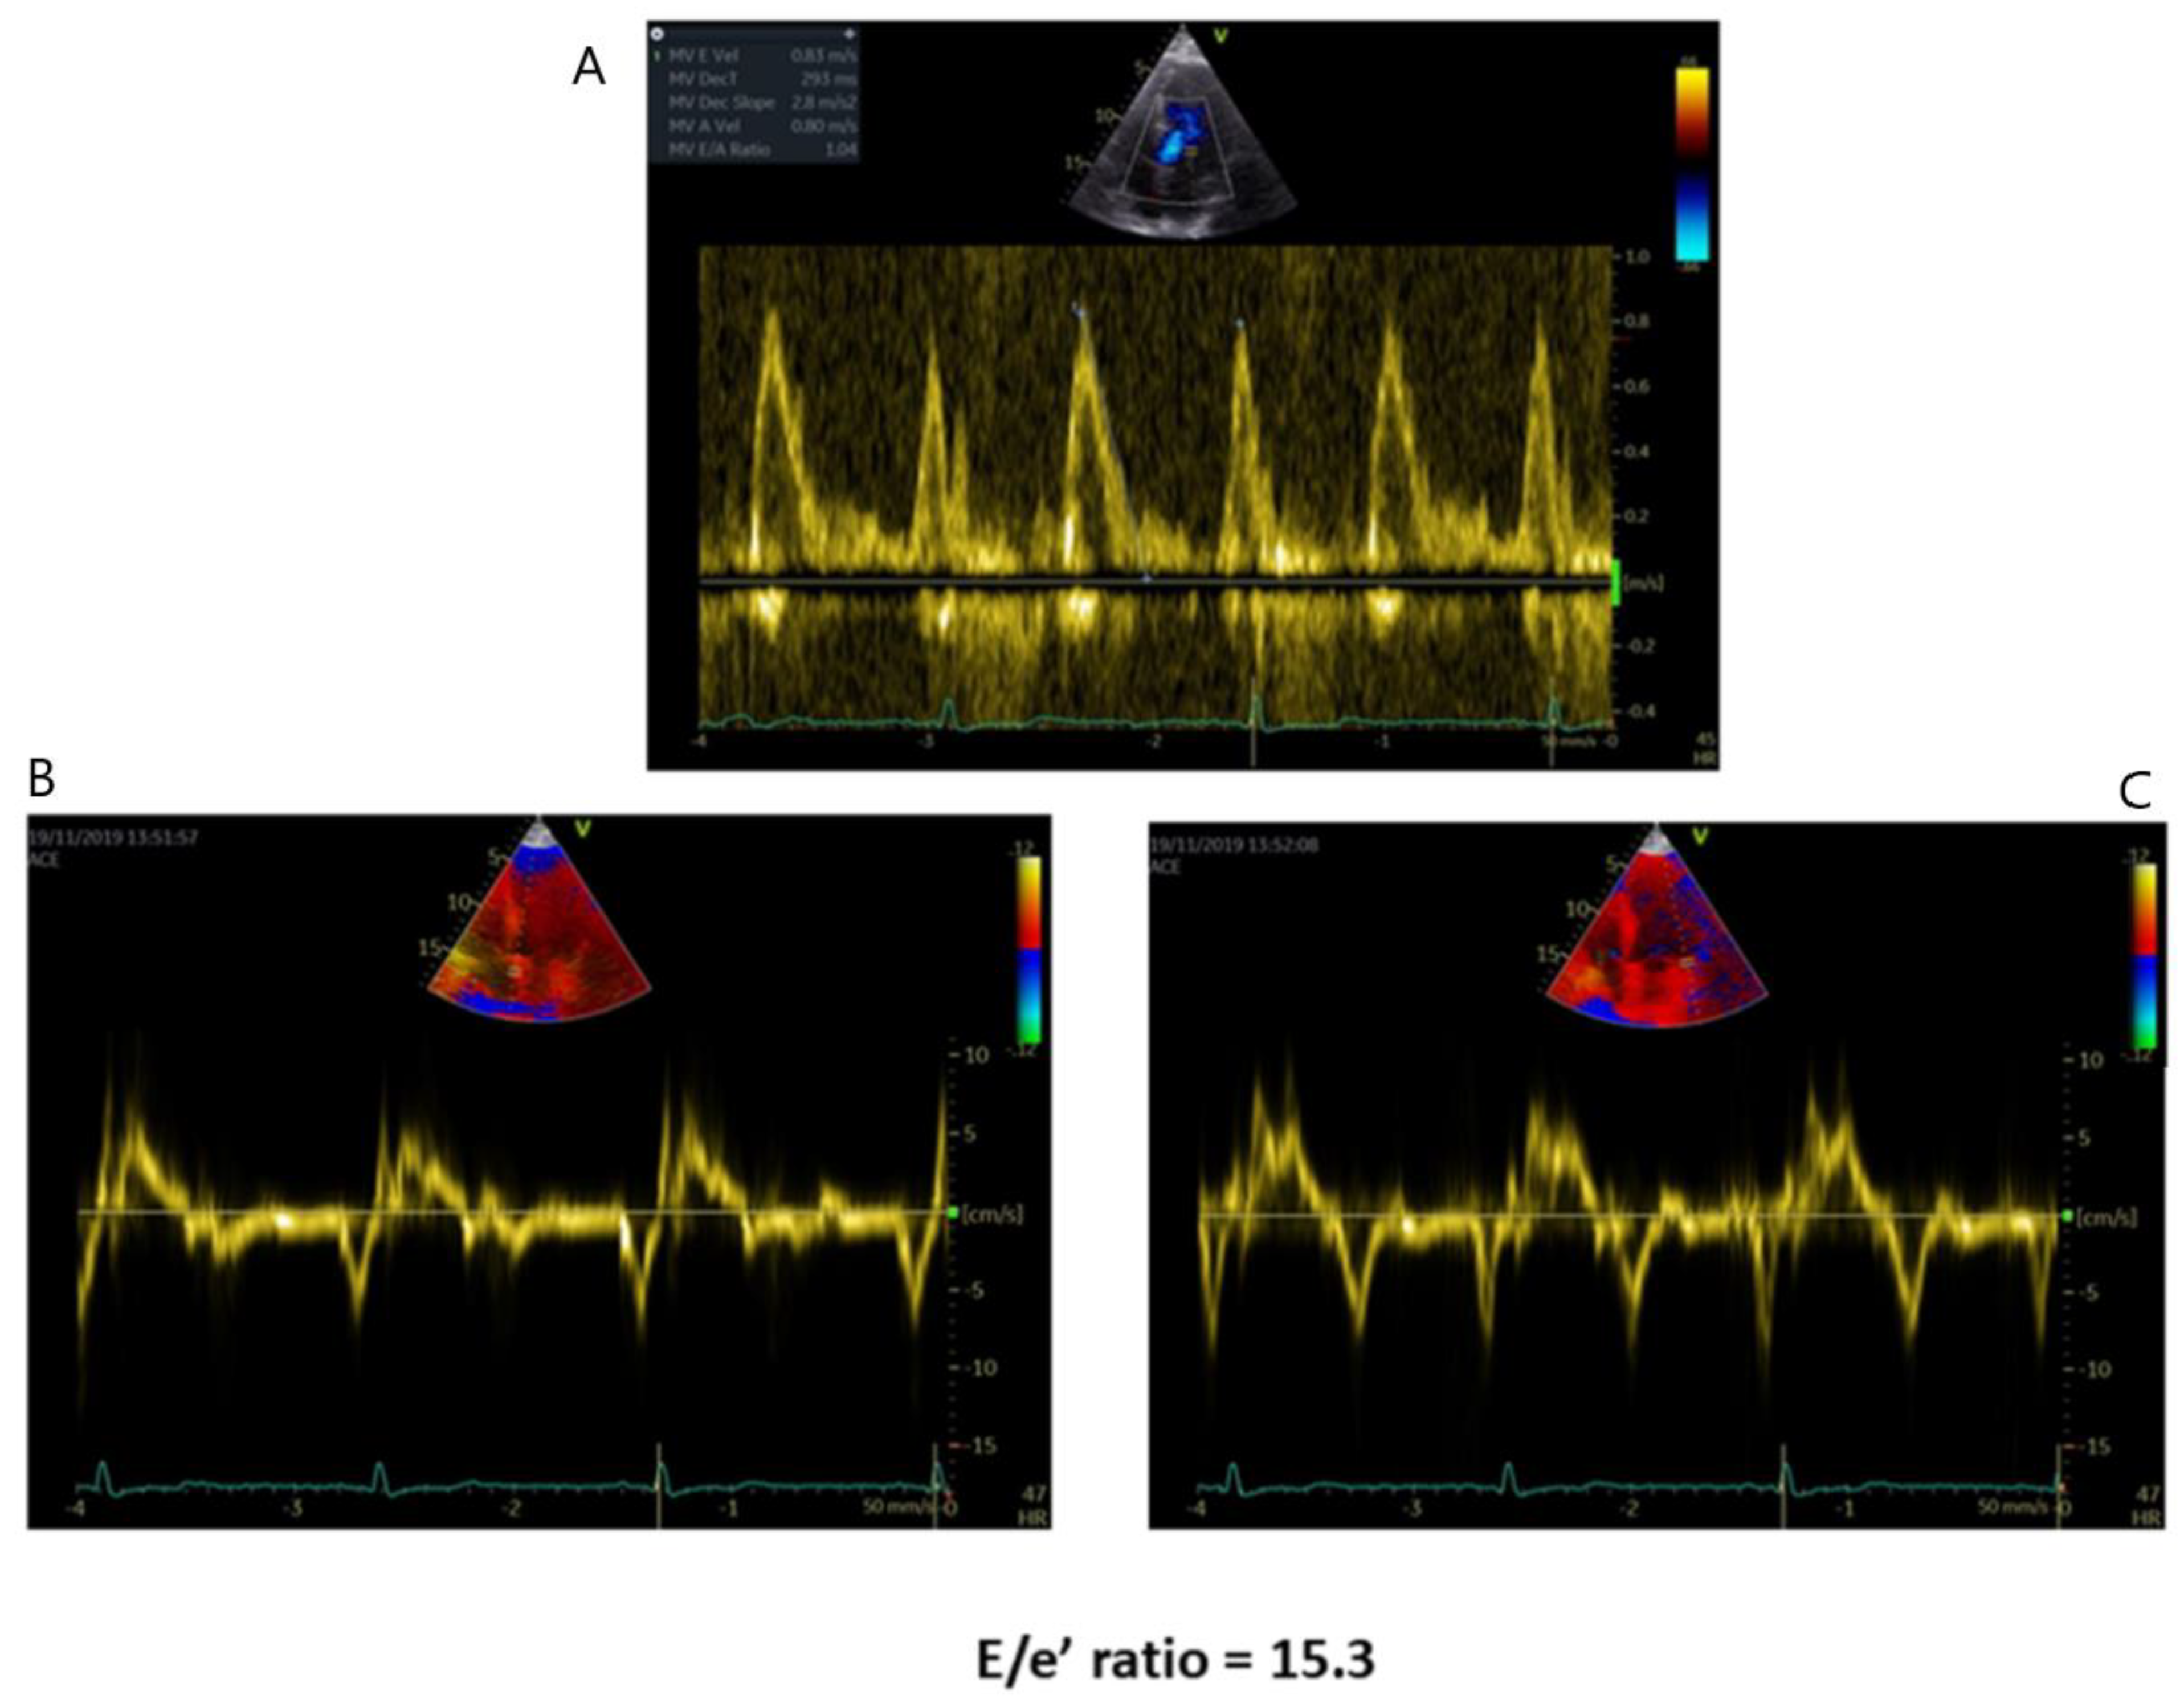

| Diastolic Dysfunction | -Mitral flow Doppler parameters alteration -E/e’ ratio increase -LA dilation | -In AFD patients with LV hypertrophy, diastolic dysfunction underlies the symptoms of heart failure |